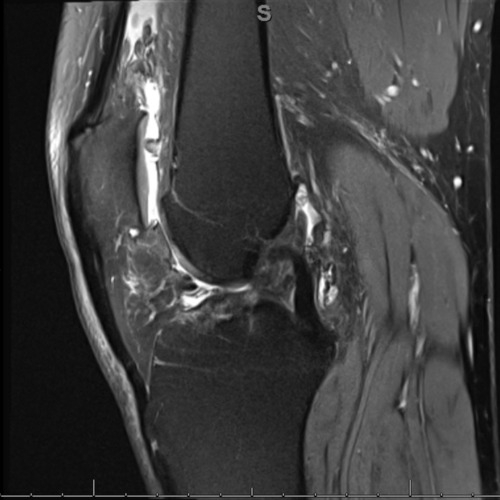

| An Unusual Cause Of Knee Swelling - Page #3 | |||